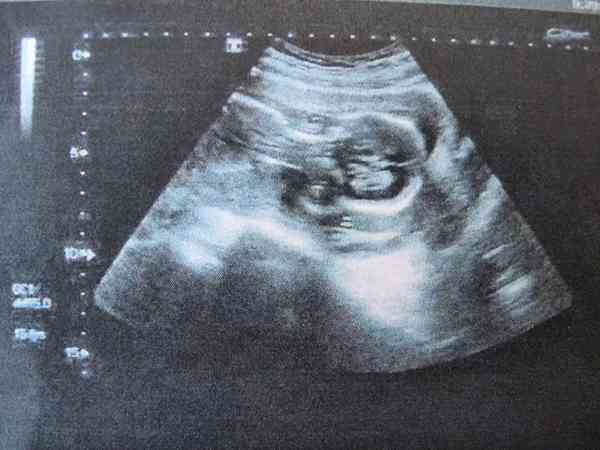

正常情況下,HCG是胚胎正常生長髮育所分泌出來的產物,也就是說只要配偶太發育正常,那麼HCG就會呈現出隔天增長一倍的情況。但是如果HCG翻倍不好的並且B超也看不見孕囊的話,就屬於異常情況,需要及時進行檢查和治療。我們都知道,女性在成功懷孕之後體內的激素水平就會有所變化,HCG含量就會隨著懷孕時間的增長呈現出翻倍增長的趨勢,並且在孕初期還可以通過B超看到孕囊。如果HCG翻倍不好並且B超中未見孕囊的話,有可能是胚胎髮育不良,也有可能是生化妊娠或者是宮外孕,需要進行進一步的檢查來確定,大家一定要引起重視。

正常情況下在女性懷孕30-40天的時候就會出現孕囊,並且HCG也會呈現出翻倍增長的情況,如果HCG增長緩慢並且檢查沒有孕囊的話,很可能就是胚胎髮育緩慢或者異常所導致的;

如果孕初期HCG翻倍不好並且在宮內也沒有看見孕囊的話,就很可能是胚胎已經生化妊娠了,需要進行進一步的檢查;

如果女性是宮外孕的話,那麼也會出現HCG增長異常並且B超檢查宮內看不見孕囊的情況,需要結合B超檢查來確定。